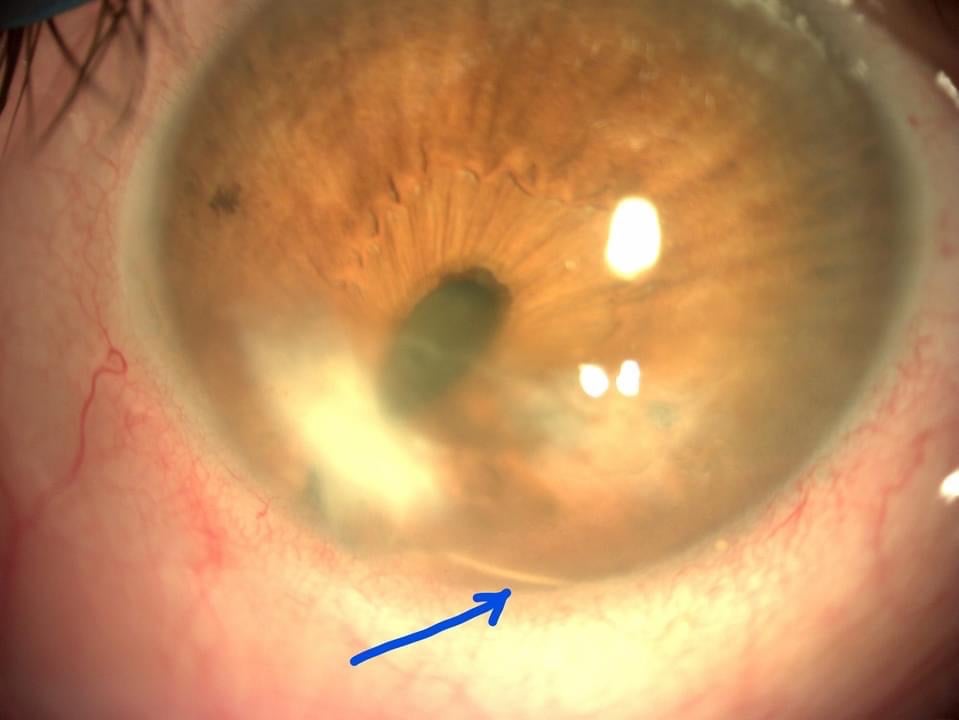

Acum câteva zile vă prezentam cazul unui pacient căruia, în urma unui traumatism perforant la ochi, i-a intrat o geană în interiorul ochiului (săgeata albastră în foto), care, împreună cu traumatismul însuși, a dus la formarea unei cataracte și a unui leucom cornean („albeață” pe cornee), precum și la deformarea evidentă a pupilei (sageata verde în foto).